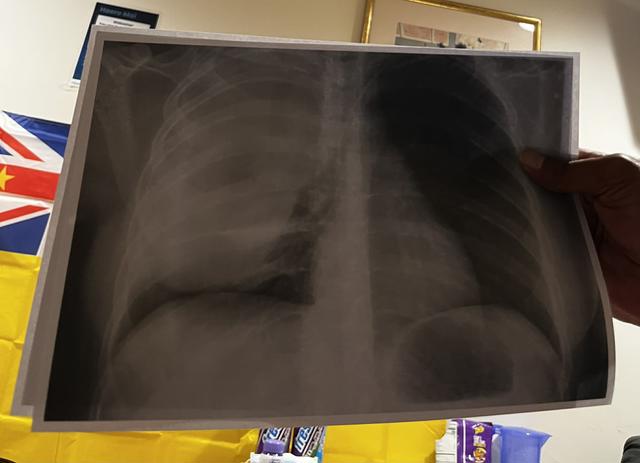

small update: had a quick xray too look at how things are going which the mass is still pretty big but there has been shrinkage & doctors said they will have a plan by next week just been doing a lot of resting these past couple of days getting my strength back.